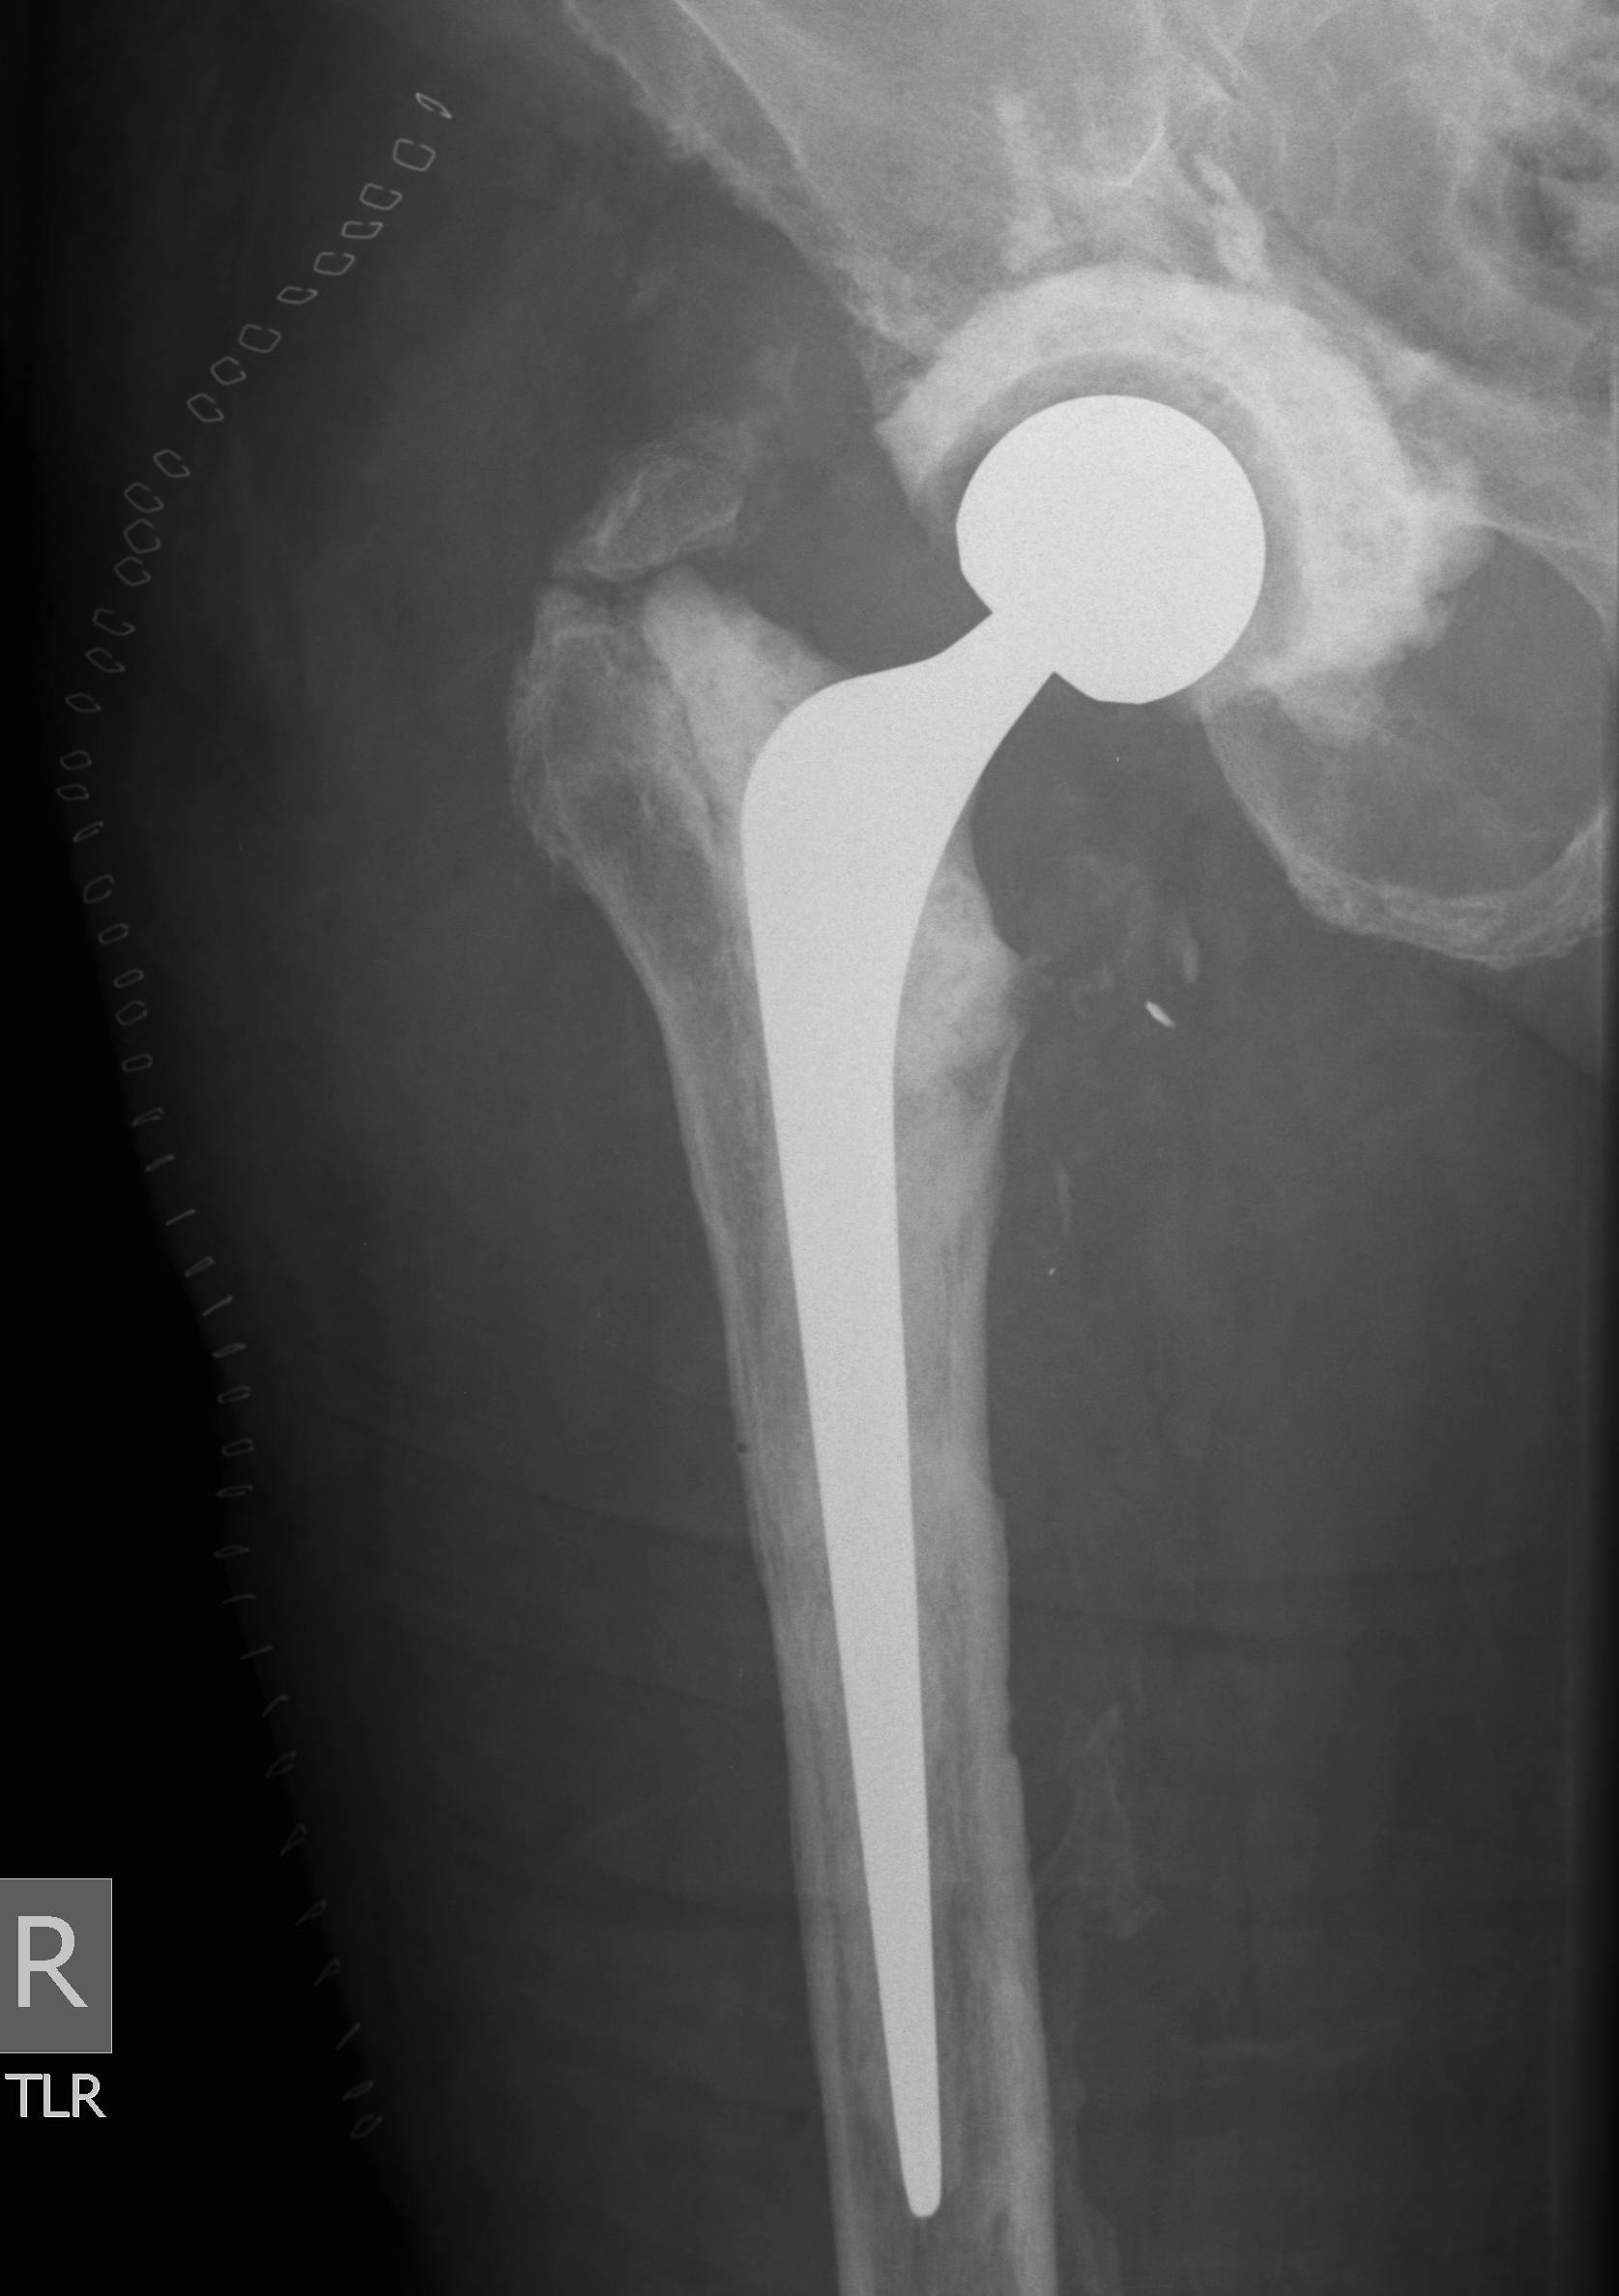

Two-Stage Revision

Technique

First stage

- debridement + removal of implants and all cement

- insert antibiotic impregnated cement spacer

Second stage

- definitive revision

- at least 2 - 4 weeks off antibiotics and normal CRP / ESR

- consider hip aspiration

- intra-operative FFS at time of surgery